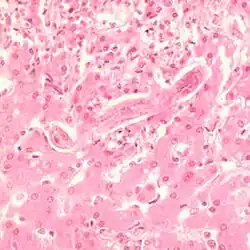

The 15 to 60 cm long and about 5 mm wide taenia taeniaeformis (hydatigera or taenia taeniaeformis, also called cat tapeworm) parasitizes in the small intestine. It is a common tapeworm in cats, only exceptionally occurring in other carnivores. The shed tapeworm members leave the anus with feces or by active migration. The coated oncospheres (mature eggs with larva L1, "six-hooked larva") are released from the dried limbs in a moist environment. These can be dispersed by flies, beetles and snails. The coated oncospheres are ingested by (obligate) intermediate hosts (rodents, squirrels) and the released six-hook larva colonizes mainly the liver of the intermediate host. It gives rise to the already tapeworm-like larva (strobilocercus fasciolaris), up to 30 cm long, which is ingested when the intermediate host is eaten. Once in the small intestine, the scolex protrudes and the tapeworm attaches itself to the intestinal mucosa. The prepatency is on average five weeks.

The rice grain-like fin stage (tetrathyridium) of mesocestoides leptothylacus can rarely occur in cats. The actual second intermediate host is common vole. Severe infestations can result in severe disease with severe weight loss (cachexia) and deaths due to peritonitis. Due to the coenurus of taenia serialis as well as the cysticercus of taenia crassiceps[13] central nervous disorders (similar to coenurosis of sheep) have been observed as a result of damage to the brain.